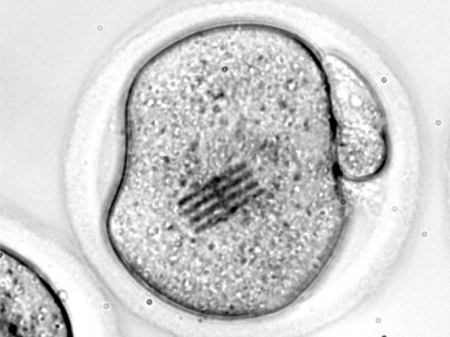

Científicos españoles fabrican chips que son inyectados en óvulos para medir las primeras fases del desarrollo embrionario

La Universidad de Granada participa en una investigación que ha permitido detectar los cambios mecánicos que se producen en los ovocitos de ratón durante las etapas tempranas de la fertilización